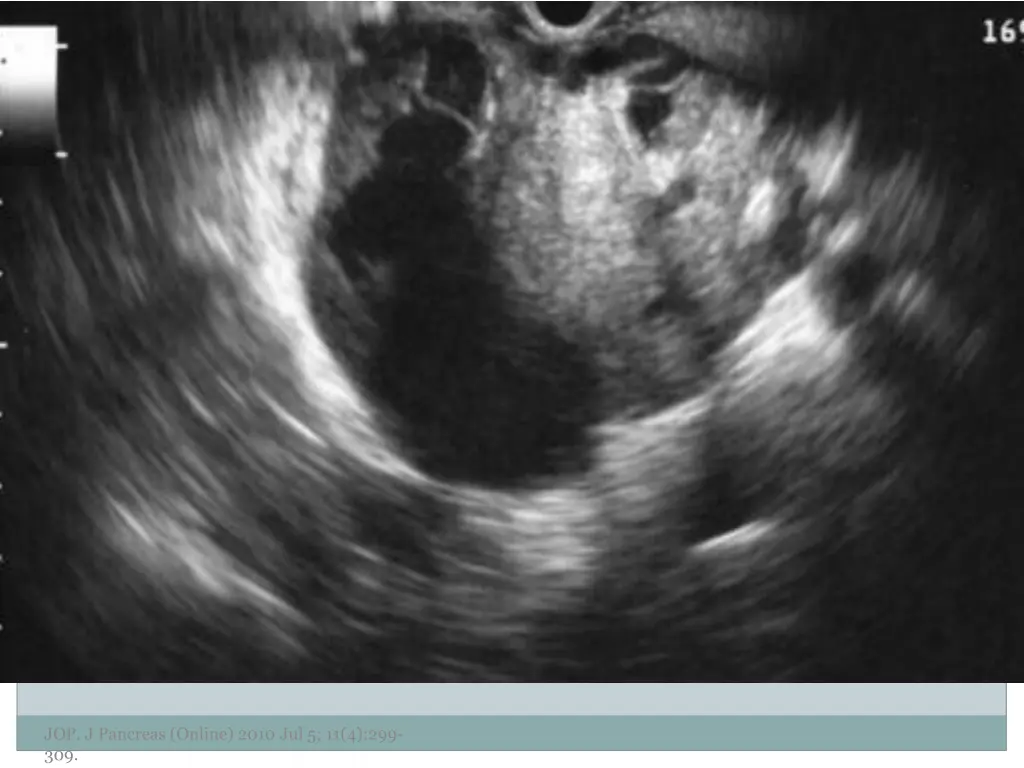

10. Examples of Morphology JOP. J Pancreas (Online) 2010 Jul 5; 11(4):299- 309.

11. JOP. J Pancreas (Online) 2010 Jul 5; 11(4):299- 309.